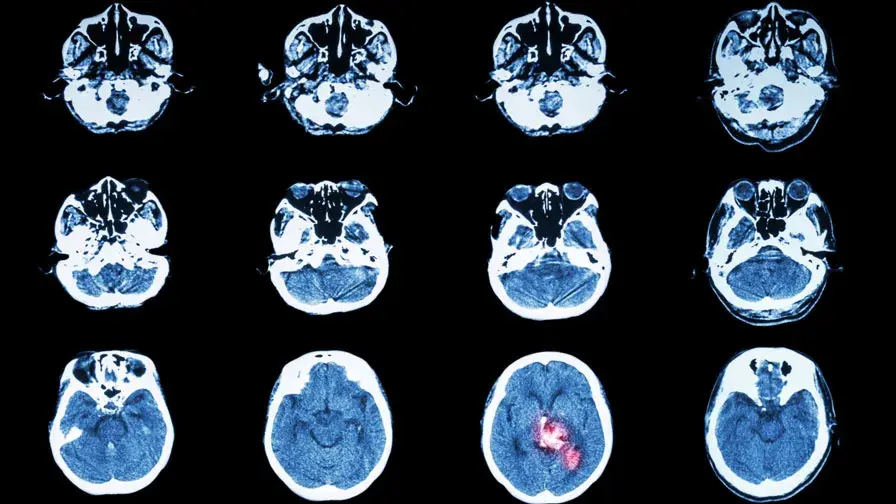

L’AP-HP inaugure le centre NEURI dédié à la prise en charge de certaines maladies du cerveau et de la moelle.

• © stockdevil/iStock/Thinkstock

• Inauguré le 4 mars 2016 en présence de Martin Hirsch, Directeur général de l’AP-HP, le centre NEURI a été ouvert à l’hôpital Bicêtre, AP-HP, avec l’Université Paris-Sud. Il permet  le diagnostic et la prise en charge, y compris en urgence, de patients atteints de maladies vasculaires du cerveau et de la moelle épinière, notamment les accidents vasculaires cérébraux - AVC.

Grâce à des équipes et du matériel de haut niveau, le centre NEURI accueille les patients en consultation ou en hospitalisation et réalise des interventions dans le cerveau ou la moelle, sous contrôle radiologique. Il s’agit du 4ème centre de neuroradiologie interventionnelle – NRI – ouvert par l’AP-HP